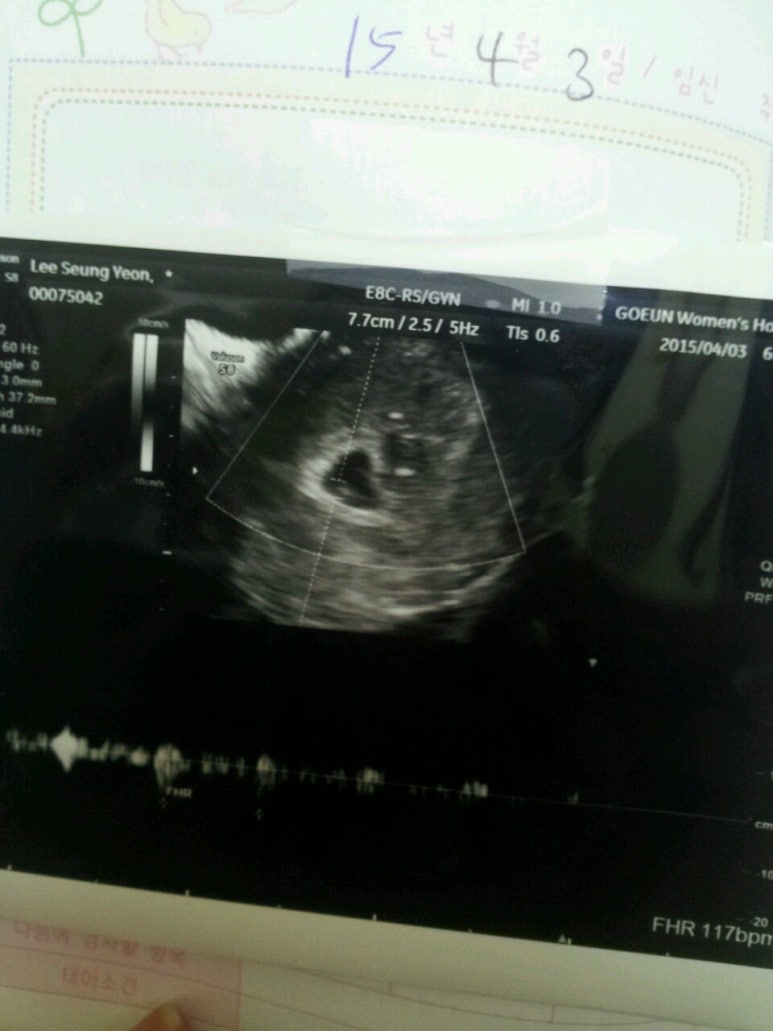

여성은 낙태 약을 사기 전에 의학적 진단을 받으셔야 합니다.